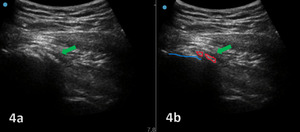

The evaluation of the gluteus medius tendon with MSKUS begins with the patient in a lateral decubitus or standing position, targeting the lateral aspect of the hip. The normal gluteus medius tendon appears as a fan shaped fibrillar structure composed of hyperechoic, striated fascicles with bright, linear bands running within the muscle.2 Pathological changes such as tendinopathy are characterized by hypoechoic (darker) regions within the tendon, tendon thickening, and loss of the normal fibrillar pattern. Tears are identified by discontinuity in the tendon fibers, with partial tears showing as anechoic (black) areas and complete tears as a full separation of the tendon from its insertion.